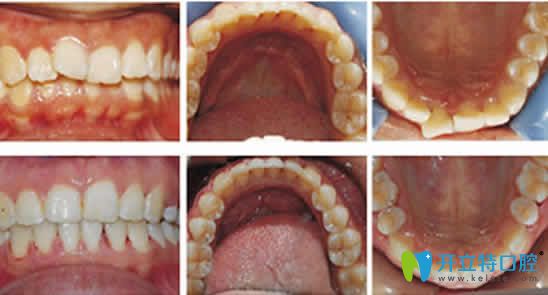

案例:鄭同學(xué),18歲;

牙齒情況:前牙外翻;

矯正方案:金屬矯正;

矯正時(shí)間:2017年10月-2018年9月;

牙齒矯正顧客鄭同學(xué)自述:自從換牙后牙齒就變的外翻,不敢開口大笑,和同學(xué)說話還捂著嘴,讓自己很自卑。在協(xié)禾口腔做牙齒矯正一年后不僅牙齒變整齊了,臉型也好看了,自己也重新變的開朗了。